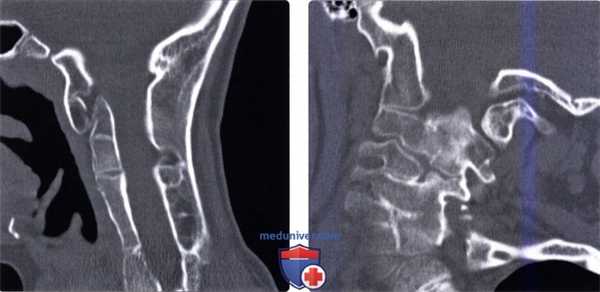

(Слева) Сагиттальный КТ-срез (тяжелая форма синдрома Клиппеля-Фейля): сращение всех шейных позвонков, а также сращение С7 с основанием черепа. Уменьшение размеров тел позвонков является типичным признаком врожденного нарушения сегментации позвонков.

(Справа) Фронтальный КТ -срез (тяжелая форма СКФ): признаки гипоплазии зубовидного отростка и сращение правых мыщелка затылочной кости, боковых масс С1 и С2. Слева боковая масса С1 не сливается ни с мыщелком затылочной кости, ни с боковой массой С2.